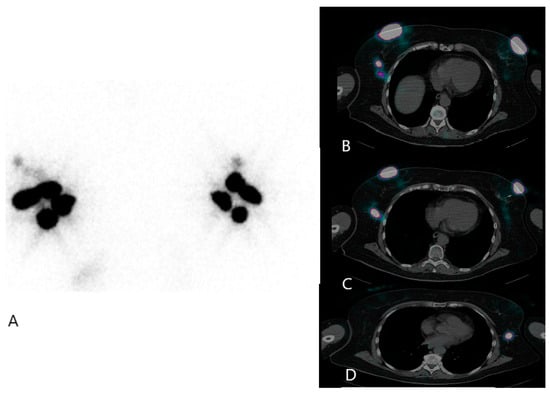

- Valdés Olmos, R.A.; Rietbergen, D.D.; Vidal-Sicart, S.; Manca, G.; Giammarile, F.; Mariani, G. Contribution of SPECT/CT imaging to radioguided sentinel lymph node biopsy in breast cancer, melanoma, and other solid cancers: From “open and see” to “see and open”. Q. J. Nucl. Med. Mol. Imaging 2014, 58, 127–139. [Google Scholar]

- Jimenez-Heffernan, A.; Ellmann, A.; Sado, H.; Huić, D.; Bal, C.; Parameswaran, R.; Giammarile, F.; Pruzzo, R.; Kostadinova, I.; Vorster, M.; et al. Results of a Prospective Multicenter International Atomic Energy Agency Sentinel Node Trial on the Value of SPECT/CT Over Planar Imaging in Various Malignancies. J. Nucl. Med. 2015, 56, 1338–1344. [Google Scholar] [CrossRef] [PubMed]

- Mucientes Rasilla, J.; Farge Balbín, L.; Cardona Arboniés, J.; Moreno Elola-Olaso, A.; Delgado-Bolton, R.; Izarduy Pereyra, L.; Rodríguez Rey, C.; Lapeña Gutiérrez, L.; González Maté, A.; Román Santamaría, J.M.; et al. SPECT-TAC: Una nueva herramienta para la localización del ganglio centinela en pacientes con cáncer de mama [SPECT-CT: A new tool for localisation of sentinel lymph nodes in breast cancer patients]. Rev. Esp. Med. Nucl. 2008, 27, 183–190. [Google Scholar] [CrossRef] [PubMed]